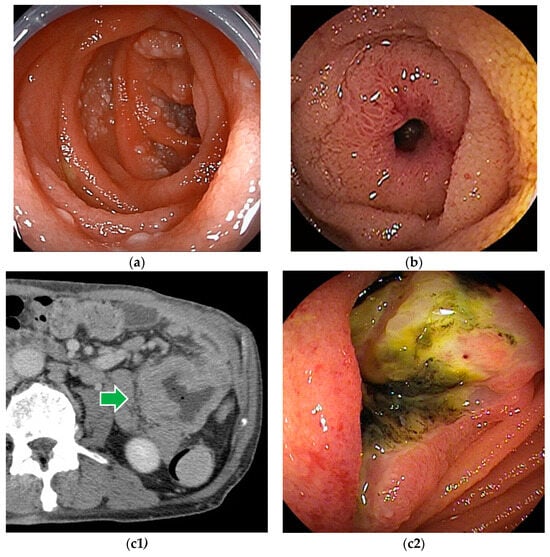

Figure 2.

Gastrointestinal stromal tumor (GIST): (a1–a3) Contrast-enhanced CT revealed a well-enhanced lesion. DBE showed a submucosal tumor covered by normal mucosa. (b) In patients with bleeding symptoms, erosions, ulcers, or dilated blood vessels are seen on the surface.

Although GIST with intraluminal and mixed patterns can be detected by BAE (Figure 2), GIST with extraluminal patterns is hardly detected by endoscopy, except for abnormal vessels and unnatural traction findings due to lesions.